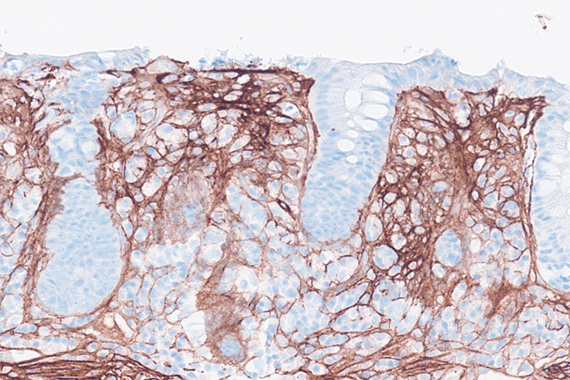

Colon biopsies in a 87 year-old female with chronic watery diarrhea.

Collagenous colitis with giant cells.

An 87-year-old woman presented with chronic, non-bloody, watery diarrhea and underwent colonoscopy, which revealed no endoscopic abnormalities. Biopsies were taken.

Histology of several colonic sites showed a thickened subepithelial collagen band (>10 μm), predominantly beneath the superficial epithelium but also surrounding the crypts (Panel A). Surface epithelial injury was also observed, with focal mucin depletion and detachment of superficial epithelial cells (Panel B). Lamina propria showed increased cellularity, with lymphocytic and plasmocytic infiltration, along with numerous giant cells (Panel C). There was no crypt architectural distortion. The collagen deposition was highlighted by Masson’s trichrome stain (Panel D) and strongly by tenascin immunohistochemistry (Panel E).

Histological variants of both collagenous and lymphocytic colitis have been described, including collagenous colitis with giant cells. In this variant, multinucleated giant cells are abundant and scattered throughout the lamina propria, with no apparent prognostic value.